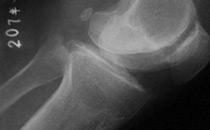

膝关节

例子

病症描述:AS在18岁前发病常导致四肢关节——尤其是膝关节——肿大疼痛。